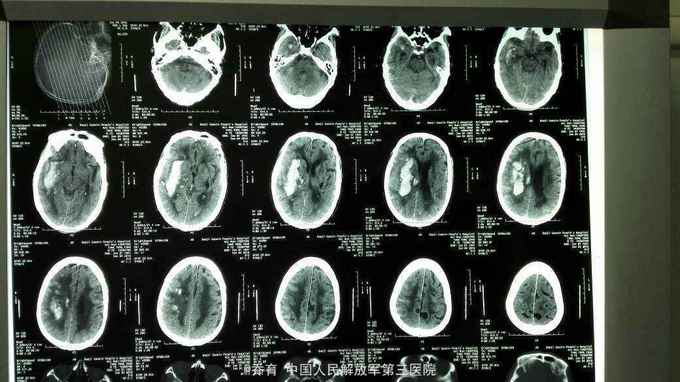

突发意识不清25小时入院,颅脑CT提示右侧基底节脑出血,量约35ml,左侧基底节区脑软化。胸部CT提示慢支,肺气肿,肺大泡,双下肺感染伴纤维化。

患者入院后急诊局麻下行脑内血肿穿刺引流术,术后给予止血,化痰,营养神经,营养支持等治疗。术后第二天复查CT提示出血大部分引出。